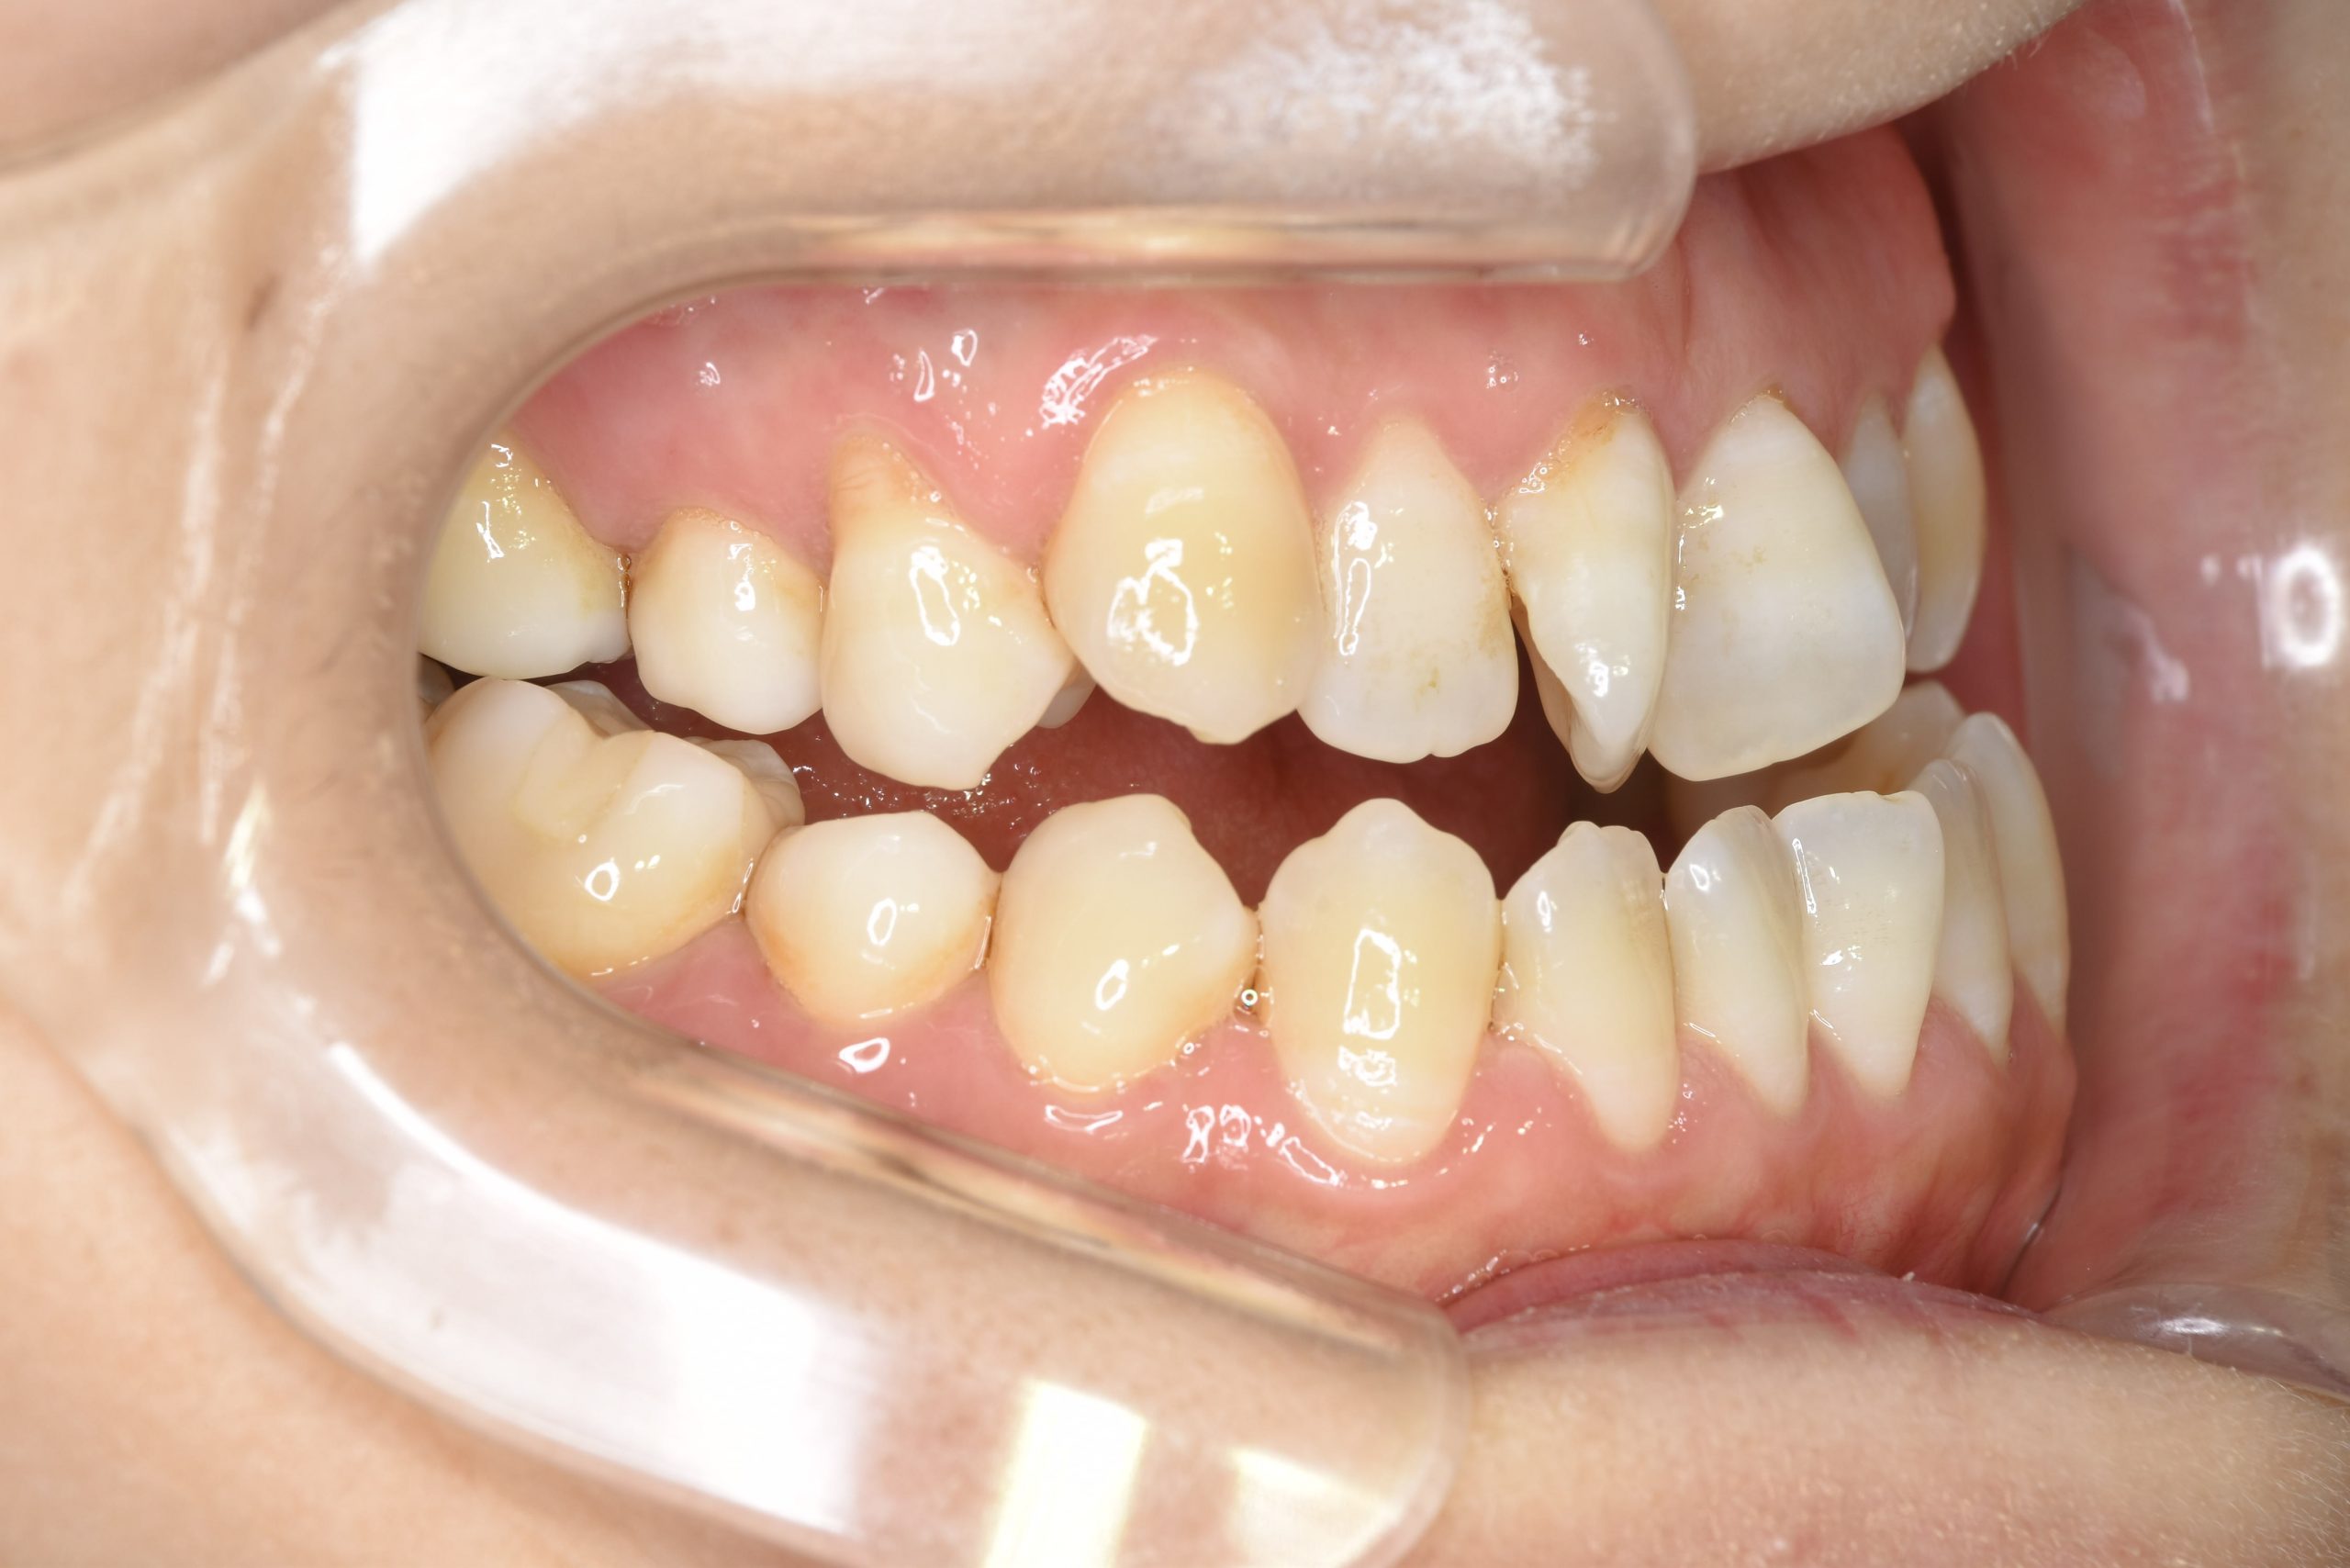

ビフォー

保険での矯正治療|症例_138

主訴 噛み合わせが悪い(反対)|歯並びが悪い|顎が出ている

施術内容 マルチブラケット装置を用いて歯牙を配列した後、

下顎骨離断術を行った。良好な咬合を獲得した。

治癒期間 3年8ヶ月間

費用 保険治療

リスク・副作用 違和感、不快感、痛み